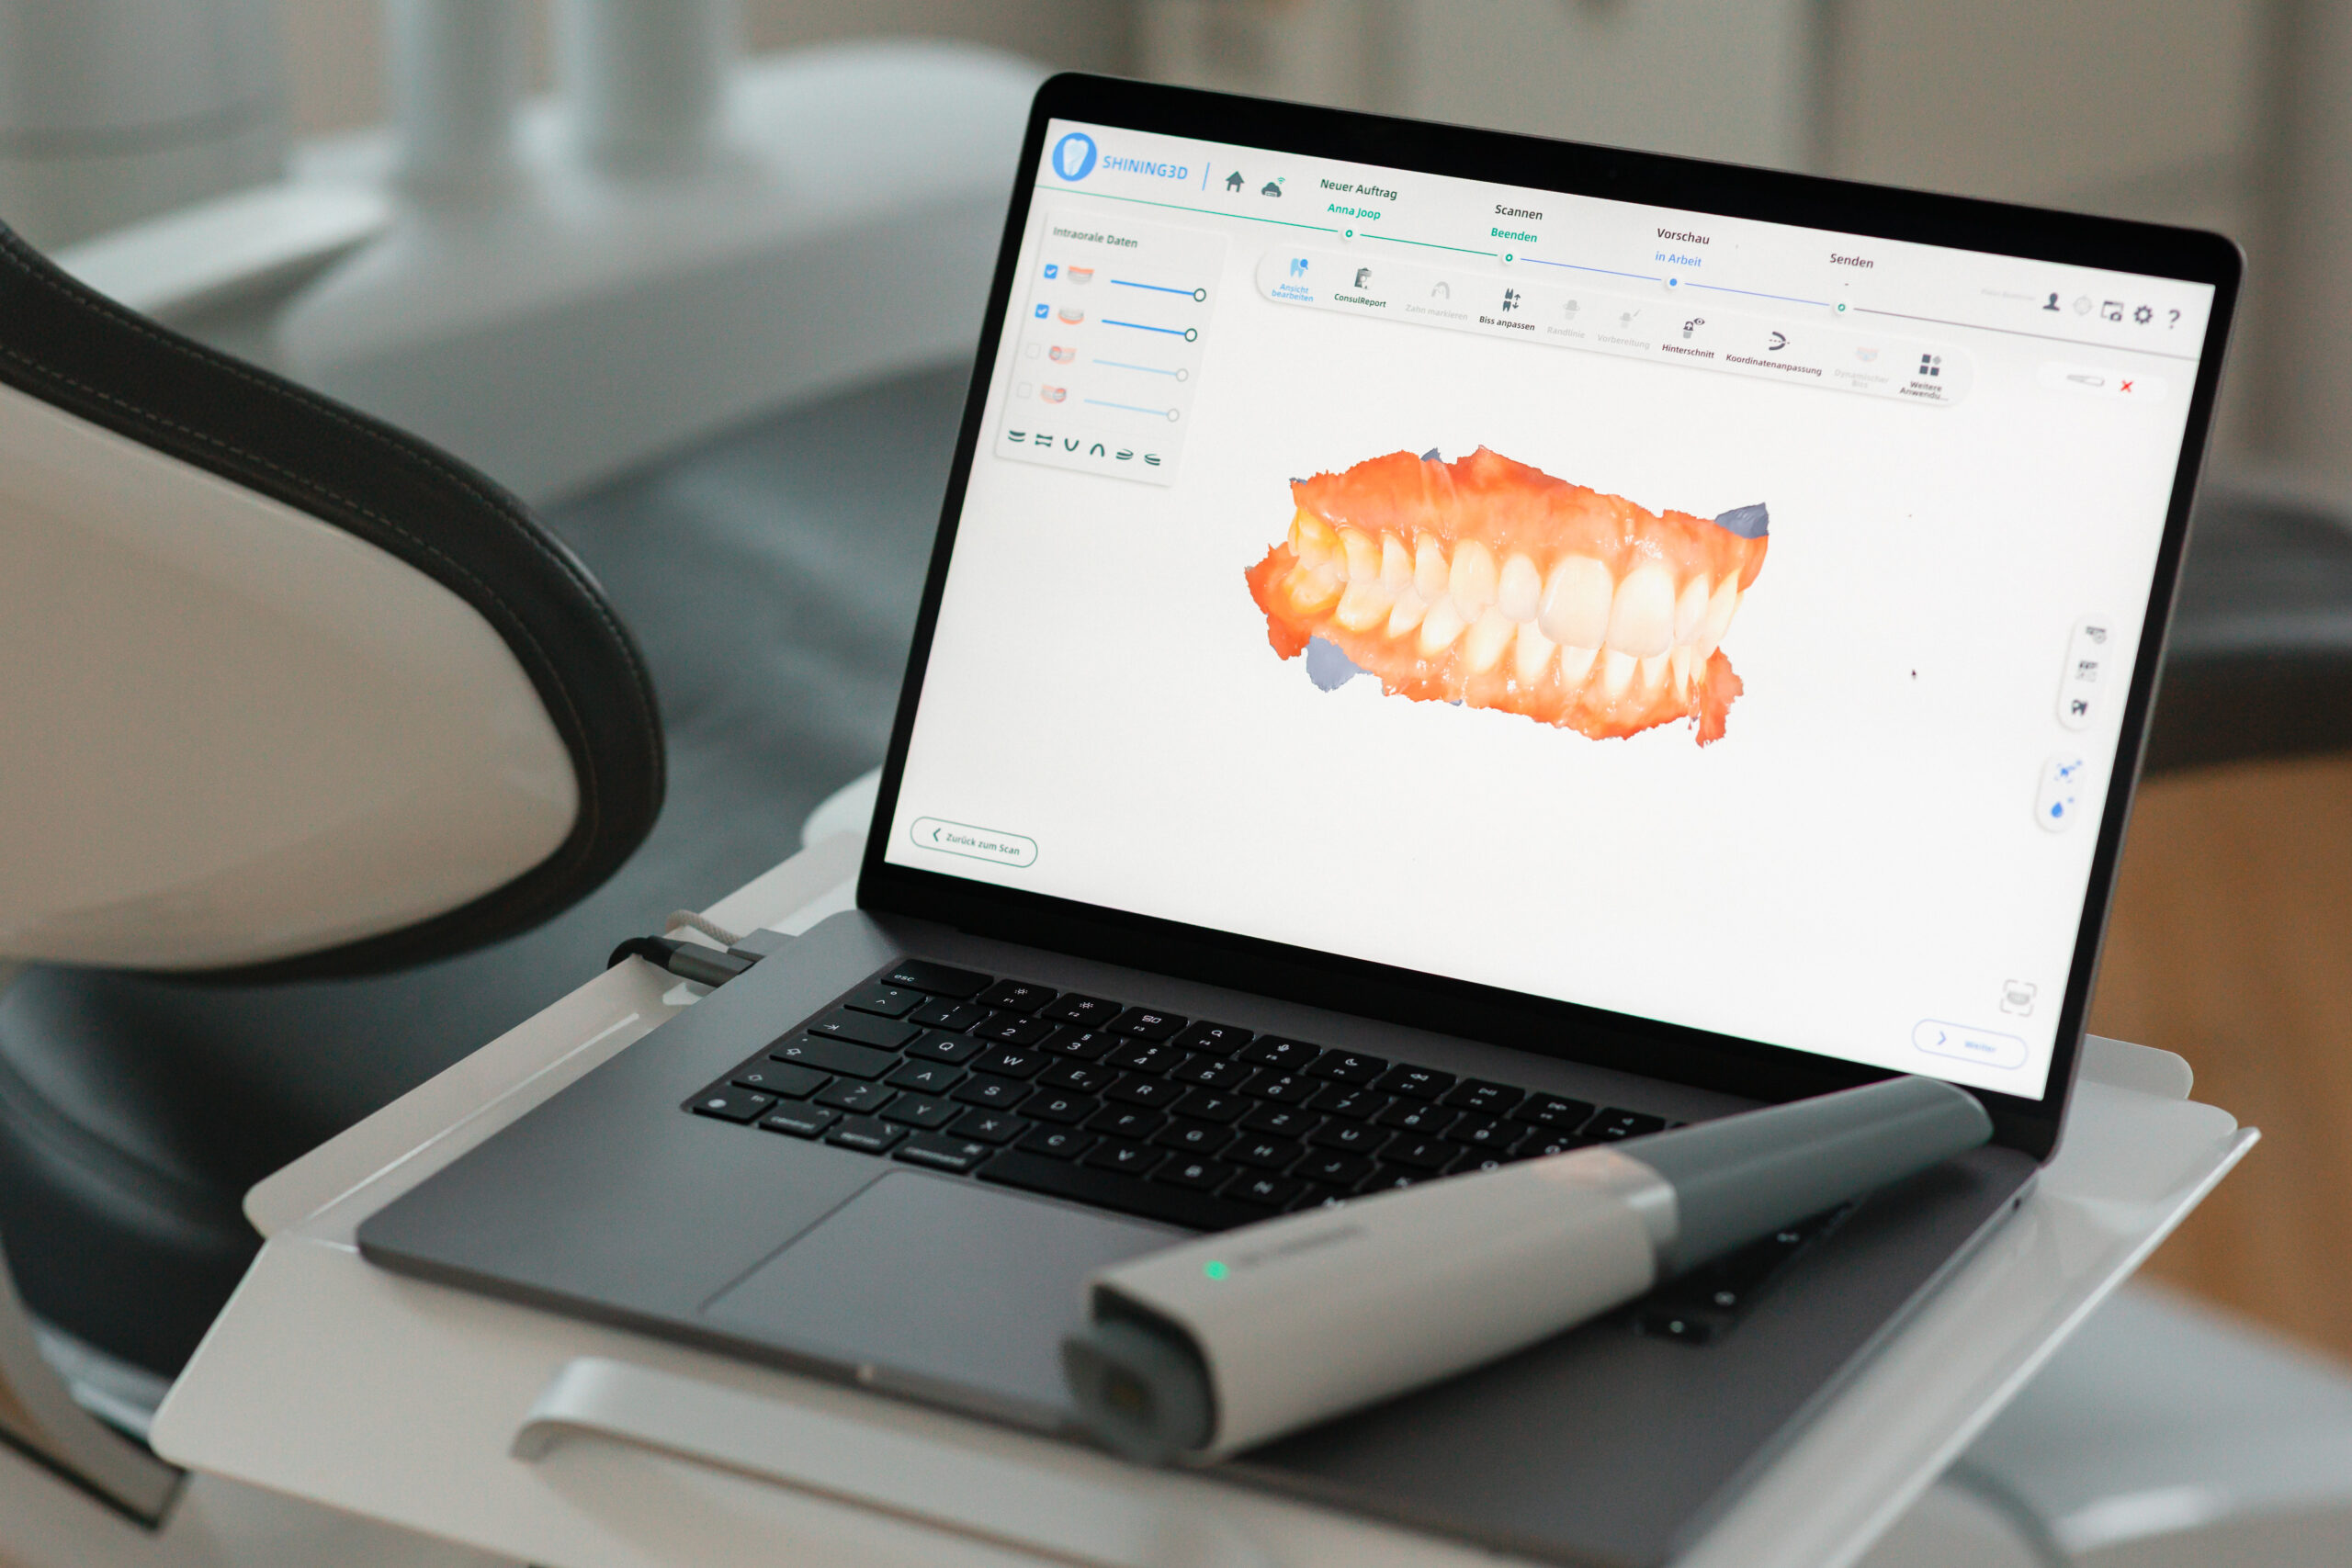

Moderne Technik ermöglicht heute eine deutlich komfortablere und genauere Erfassung Ihrer Zähne. Die digitale Abformung ersetzt den klassischen Abdruck und die unangenehme Abdruckmasse. Ergänzend liefern intraorale Fotos hochauflösende Einblicke, die Diagnose, Planung und Ihr eigenes Verständnis der Behandlung verbessern.